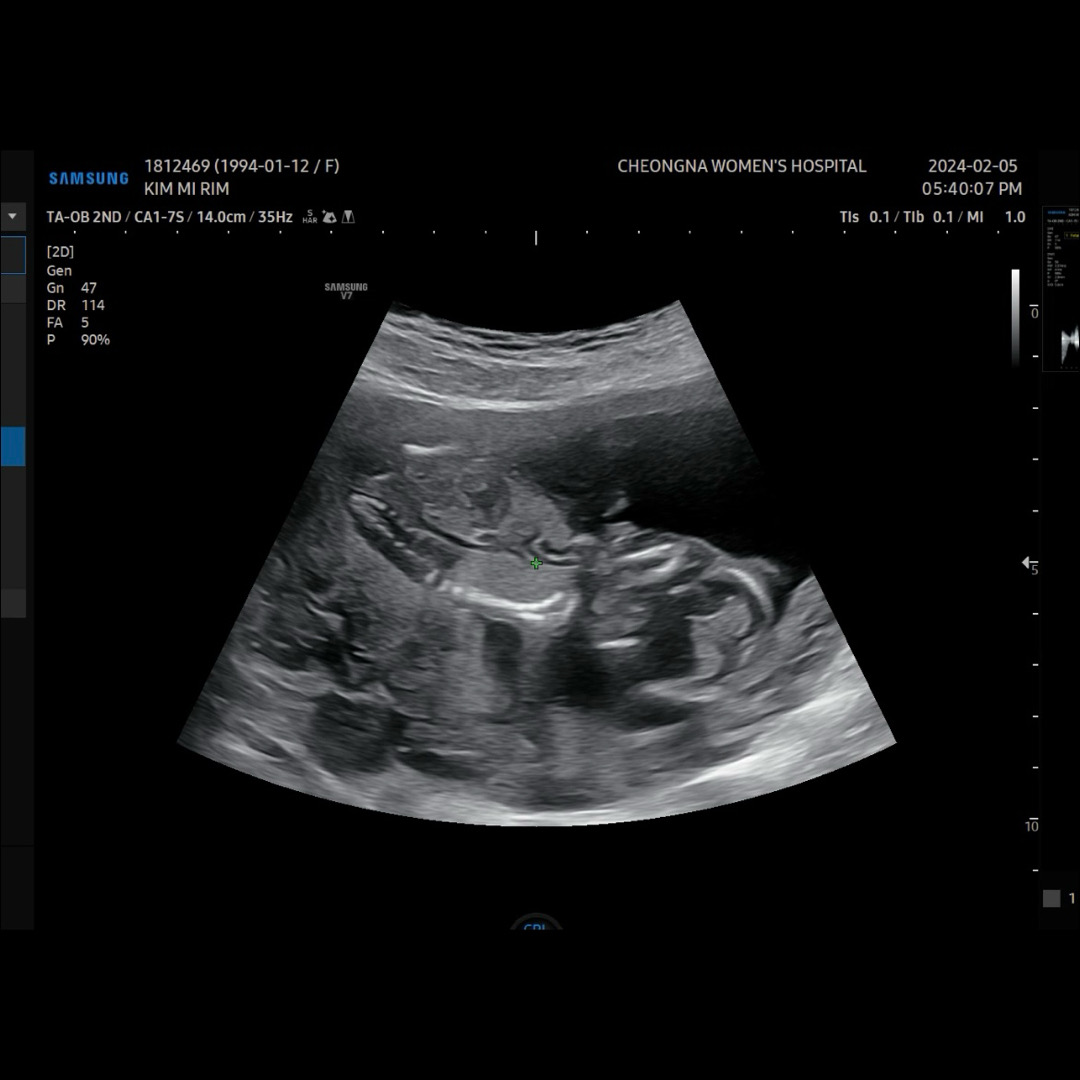

14주 1일차 인데 오늘 초음파 봤는데 약간 고추 생기는 것 같대요 ㅋㅋㅋㅋㅋ

살짝 딸래미를 바랬지만 ㅎㅎ ㅠㅎㅎㅎㅎ 아들도 좋아요~~~~~ 양반다리 하고 있어서 제대로 안보이긴 하지만 의사선생님께서 꼬추 생기는 것 같다고 말씀하시더라구요 하항 뭐 다음에 초음파 보러 갈 땐 정확히 알겠죠^_^